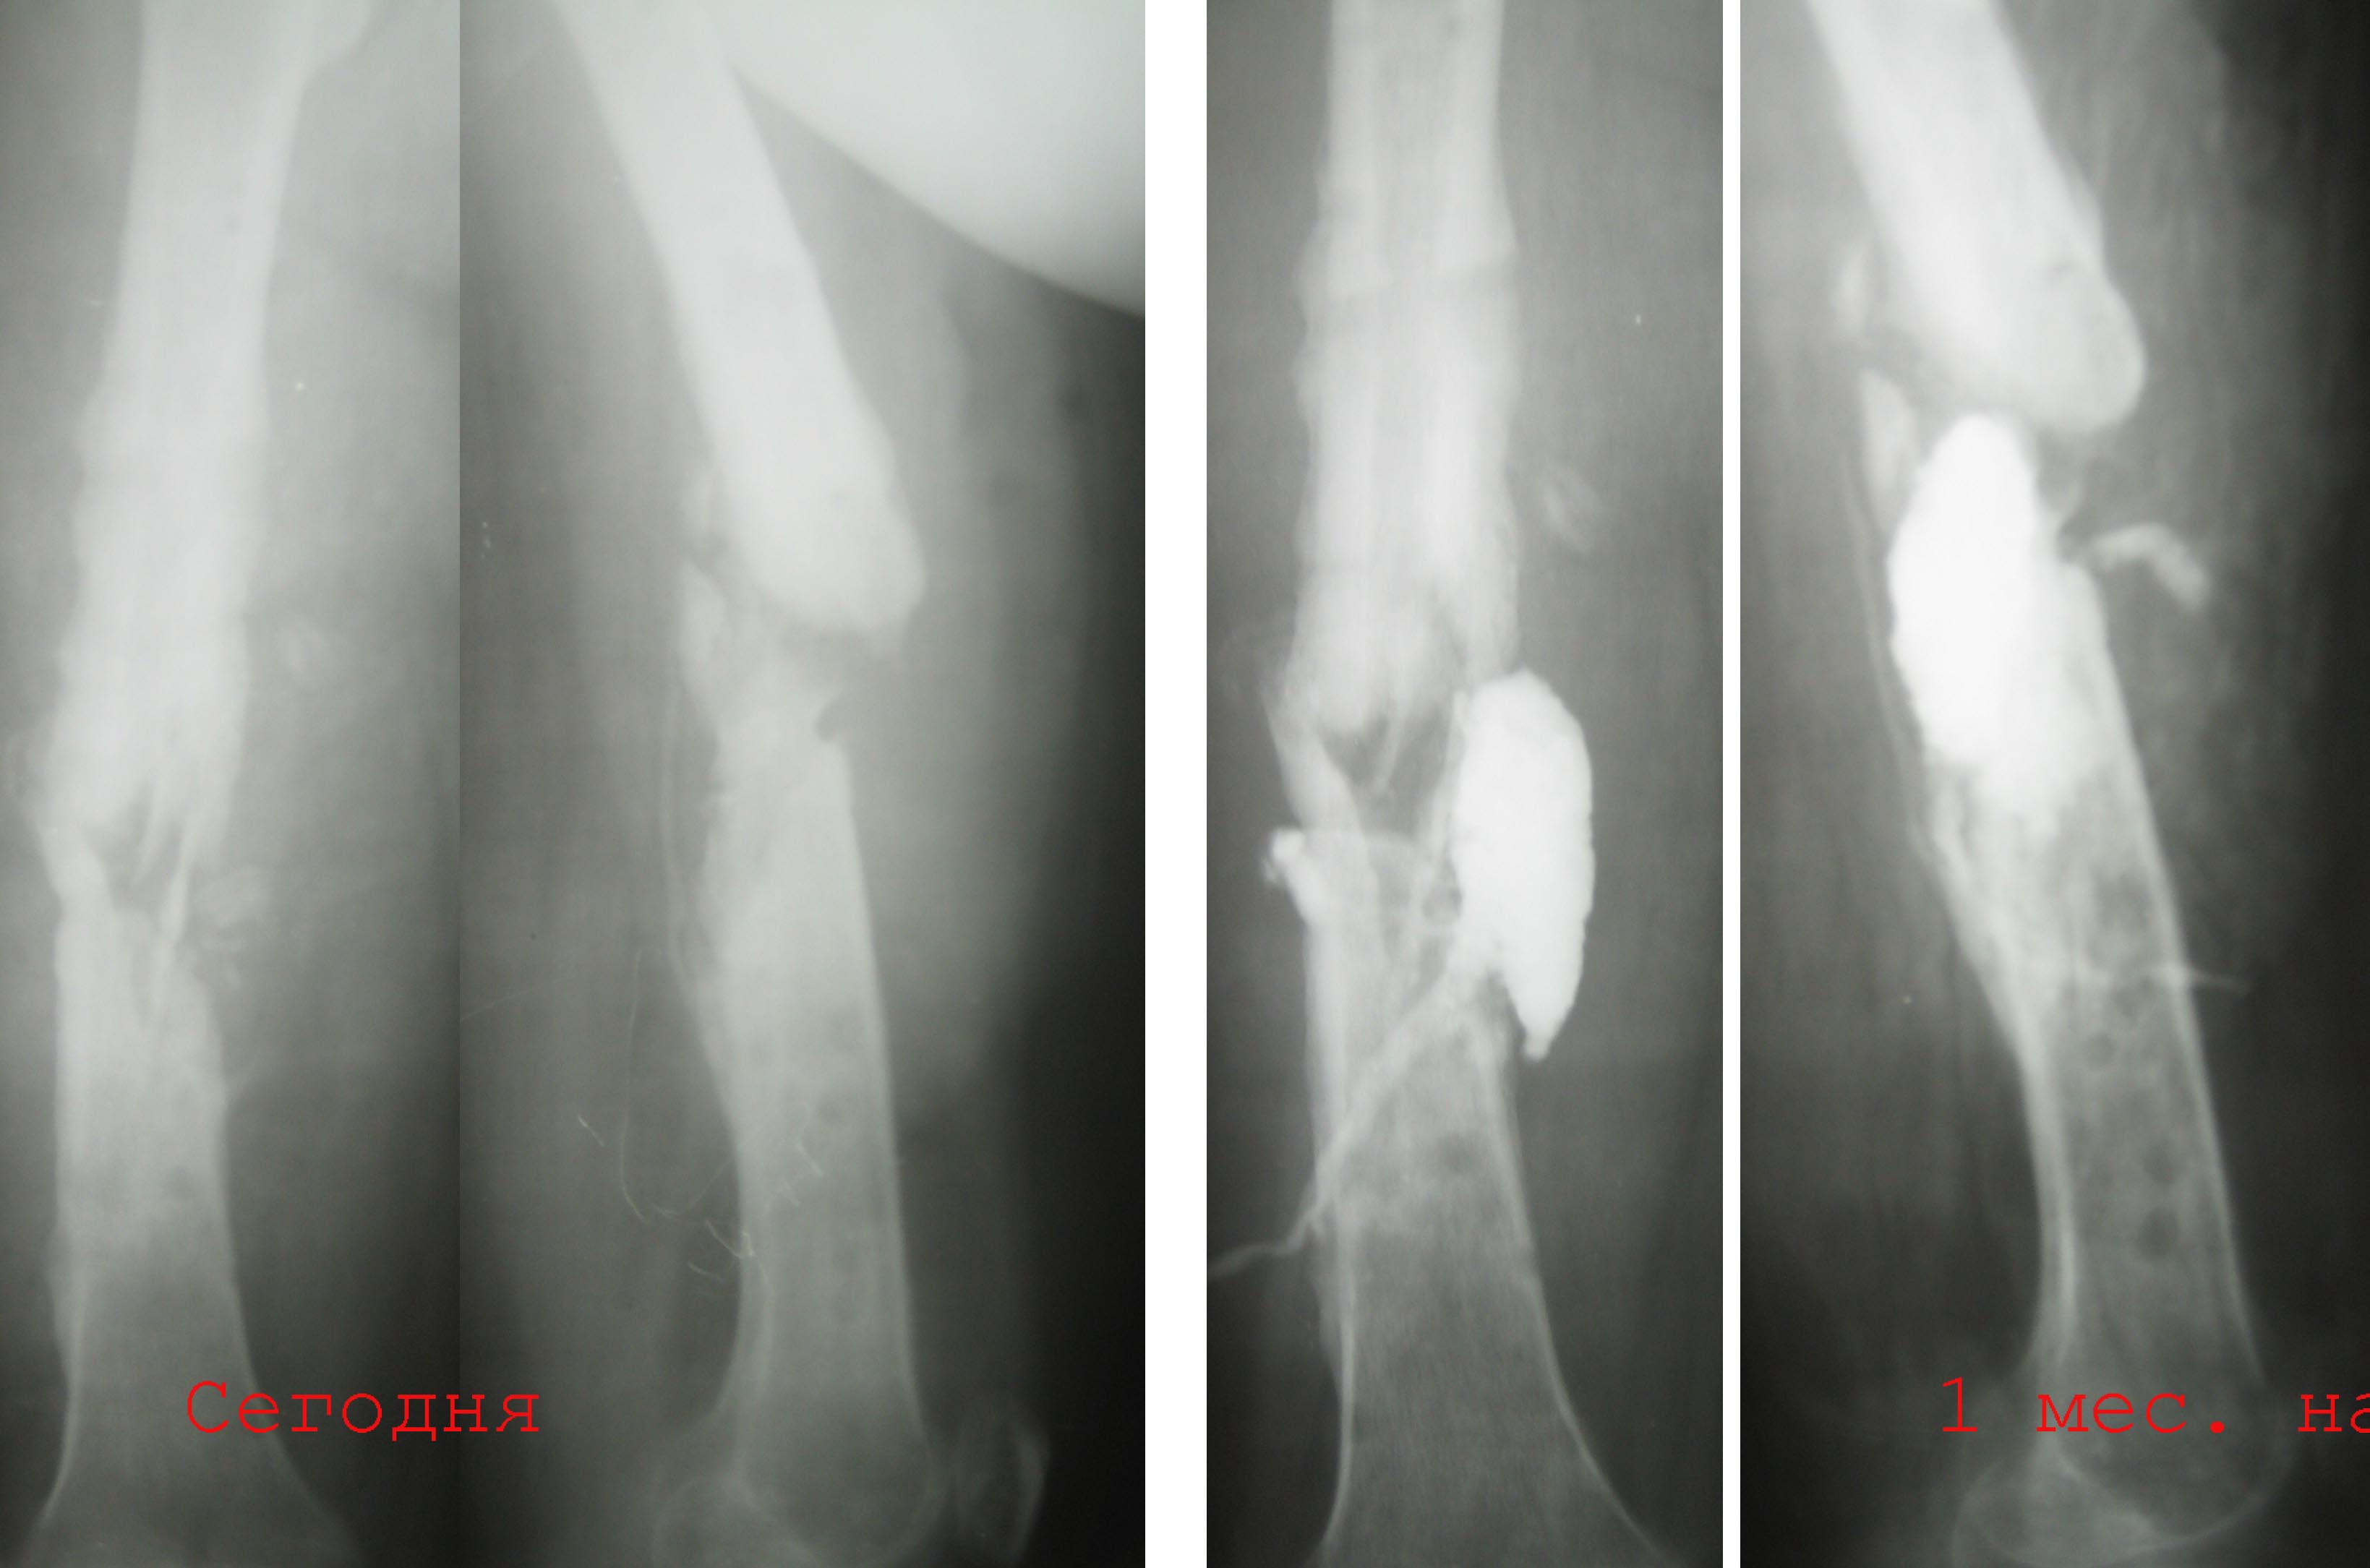

1. 14 мес назад (летом 2008 г)- перелом бедра, оскольчатый, закрытый. Интрамедуллярный

остеосинтез гвоздем Кюнчера, несостоятельная фиксация, поэтому

дополнили кокситом.

2. Через 4 мес. ввиду отсутствия перспектив сращения - я выполнил остеосинтез

аппаратом Илизарова. В отдельные периоды была надежда на

консолидацию. В аппарате 6-7 мес, постоянные выделения в области

стержня - сняли аппарат.

3.  2 мес. ходит с лонгетой, имеется патологическая подвижность. В

течение месяца после снятия сохранялись выделения из отверстия, где

был стержень, температура до 38, иногда отсутствовала. Сделал

фистулу с уверенностью, что это стержневой остеомиелит.

Но контраст ушел в зону перелома, и эвакуировал около 20 мл

лизированной крови (без гноя). Температура исчезла, свищ практически

закрылся.

4.  Сейчас два раза в неделю промываем эту полость, всегда - около 7 мл

сукровицы. Иногда - Субфебрильная температура.

Имя     : Бедро фистула.jpg